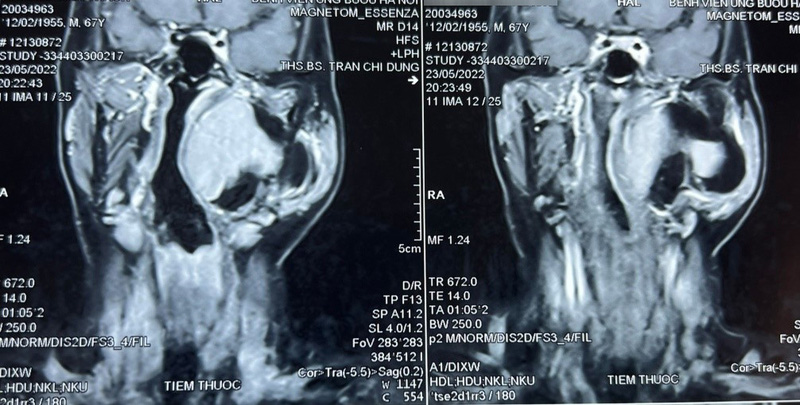

Qua thăm khám và đánh giá, bác sĩ phát hiện một khối u lớn vùng cổ kích thước khoảng 10×8 cm, thuộc khoảng bên họng, trải dài từ nền sọ xuống hạ họng, đẩy lệch thành bên họng vào trong, gồm 2 phần: phần nông nằm dưới tuyến mang tai và phần còn lại nằm sâu hơn. Chẩn đoán sơ bộ ban đầu khối u là lành tính, ranh giới không rõ ràng.

Thông qua hội chẩn, các bác sĩ quyết định tiến hành phẫu thuật sớm lấy bỏ khối u tránh nguy cơ khối u chèn ép vào đường thở, đường ăn, thần kinh, mạch máu và các thành phần liên quan khác. Tiên lượng cuộc mổ là rất khó khăn, đường tiếp cận chính là qua mổ mở từ vùng cổ, phải thực hiện các thao tác phẫu thuật trong không gian hẹp, có thể kết hợp thêm hỗ trợ nội soi.

Theo bác sĩ Trần Chí Dũng, Khoa Ngoại Đầu cổ, khoảng bên họng là khoang giải phẫu kéo dài từ nền sọ tới vùng họng miệng. U khoảng bên họng là loại ít gặp trong vùng đầu cổ, chiếm khoảng 1%. Tỉ lệ u lành chiếm chủ yếu (70 – 80%), còn lại (20 – 30%) là u ác tính. Dù là u lành hay ác tính thì phương pháp điều trị chính đều là phẫu thuật.

Do đặc điểm giải phẫu phức tạp, nằm trong vùng cổ sâu, liên quan hầu hết thần kinh, mạch máu lớn và các thành phần quan trọng khác của đầu cổ, phẫu thuật u vùng khoảng bên họng luôn là loại khó khăn bậc nhất trong chuyên khoa phẫu thuật đầu cổ.